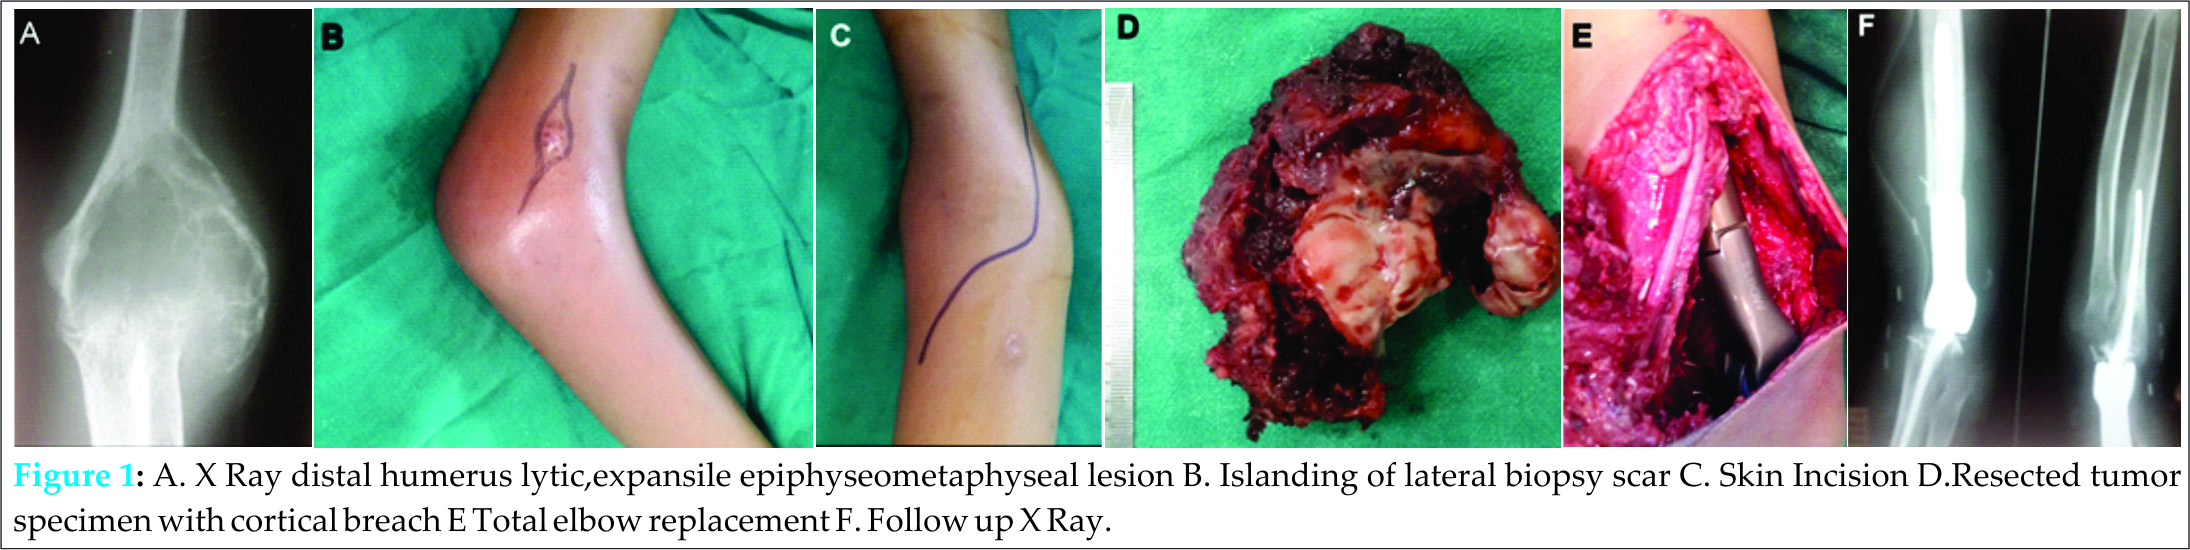

Both patients had Campanacci grade III giant cell lesions and were managed surgically. As Case 1 had cortical breach in multiple planes, large soft tissue component, total physeal destruction, large area of subchondral bone involvement, hence wide resection with total elbow replacement was planned [Fig.1].

Case 2 had minimal cortical breach and a small soft tissue component. Hence this patient was managed by extended curettage, cementation and plate-screw construct augmentation. There was wound dehiscence at six weeks in this patient which was managed by gasrtrocnemius flap [Fig.3]. Both the patients are free of recurrence at one year follow up.